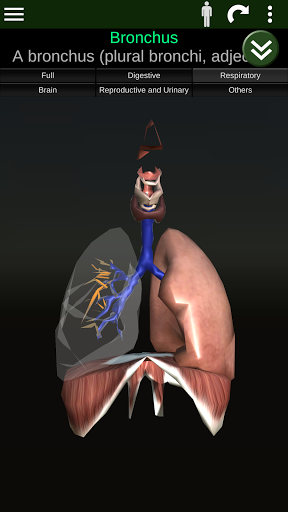

Internal Organs in 3D Anatomy لـ Vodafone Smart N9 Lite

(الأجهزة الداخلية في)

Internal Organs 3D Anatomy 3.4

يمكنك هنا تنزيل ملف حزمة تطبيق أندرويد "Internal Organs 3D Anatomy" الخاصة بجهازVodafone Smart N9 Lite مجانًا، نسخة ملف حزمة تطبيق أندرويد - 3.4 للتحميل على Vodafone Smart N9 Lite اضغط ببساطة على هذا الزر. إنه سهل وآمن. نحن نقدم فقط ملفات حزمة تطبيق أندرويد الأصلية. إذا انتهكت أية مواد موجودة في الموقع حقوقك قم بإبلاغنا من خلال